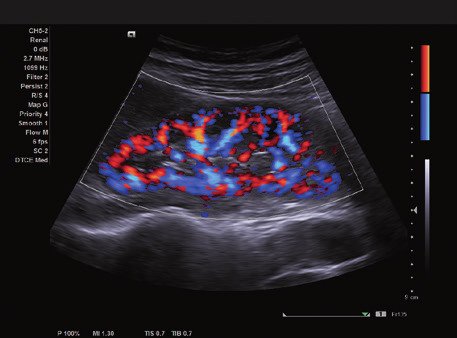

Das ACUSON NX2 Ultraschallsystem besitzt eine zukunftsfähige digitale Plattform mit nahezu unerreichter Bildqualität und sorgt für effiziente und zuverlässige Diagnosedaten. Die Vielseitigkeit des Ultraschallsystems wird mit einem großen kompatiblen Portfolio an Schallköpfen gedeckt, und so ist für jeden Anwendungsbereich etwas dabei. Die Bedienkonsole ist intuitiv aufgebaut und optimiert und erlaubt bis zu vier nach vorne gerichteten Schallkopfanschlüssen für eine enorme Effizienz und schnellen Workflow. So lassen sich bei der fetalen Bildgebung außergewöhnlich detailgetreue Darstellungen des Fetus im Gesicht zeigen oder durch die herausragende Farbdopplersensitivität bei der Darstellung der kleinen Gefäße des zystischen Schilddrüsenknotens kleinste Details erkennen. Weiterhin besticht das NX2 mit einfacher Aufrüstbarkeit bei wachsenden Anforderungen für Ihre zukünftigen Anwendungen und kompatible skalierbare Schallköpfe verringern ihren Kapitaleinsatz um bis zu 31 %.